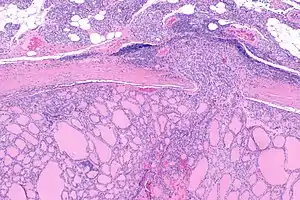

| Micrograph of follicular thyroid carcinoma showing a location where the cancer grows through the fibrous capsule. H&E stain. | |